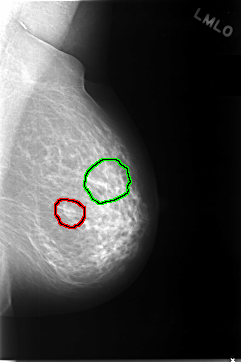

C_0038_1.RIGHT_MLO

FILE: C_0038_1.LEFT_MLO.OVERLAY

TOTAL_ABNORMALITIES 2

ABNORMALITY 1

LESION_TYPE MASS SHAPE OVAL MARGINS CIRCUMSCRIBED

ASSESSMENT 4

SUBTLETY 5

PATHOLOGY BENIGN

TOTAL_OUTLINES 1

BOUNDARY

ABNORMALITY 2

LESION_TYPE CALCIFICATION TYPE FINE_LINEAR_BRANCHING DISTRIBUTION CLUSTERED

ASSESSMENT 5

SUBTLETY 4

PATHOLOGY MALIGNANT